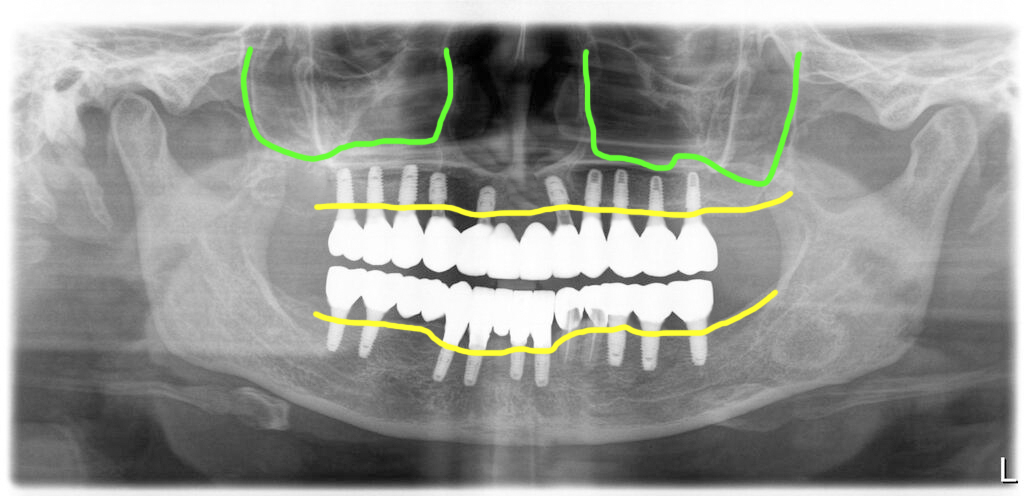

첫번째 수술 후 6개월 경과 후 두번째 수술이 진행되었습니다. 상악동에 이식해 둔 뼈상태가 좋아 식립한 임플란트의 초기고정이 안정적이어서 수술당일 임시치아를 적용하는 즉시하중 치료를 진행했습니다.

상악 전체에 10개의 임플란트를 식립해서 서로 완전하게 연결하여 PMMA 재료로 된 임시치아를 밀링해서 최종세멘트로 고정했습니다.

간혹 임시치아를 어떤 세멘트로 고정하는지 질문이 있는데 이때 임시치아는 완전히 고정이 잘 되어야 하기 대문에 최종세멘트를 사용하고 재료는 주로 광중합 레진세멘트를 이용해서 잉여세멘트 제거가 용이하게 해 줍니다.

두번째 수술 후 6개월 차에 최종보철을 위한 스캔을 한 후 최종보철을 완성해서 세팅한 모습입니다.

아래 남긴 2개의 치아는 크라운을 했으며 최종보철을 할 때에는 임플란트와 분리해 주어야 합니다. 자연치와 임플란트는 분리하는 것이 원칙입니다. 아주 예외적인 상황을 제외하고는 그렇습니다.